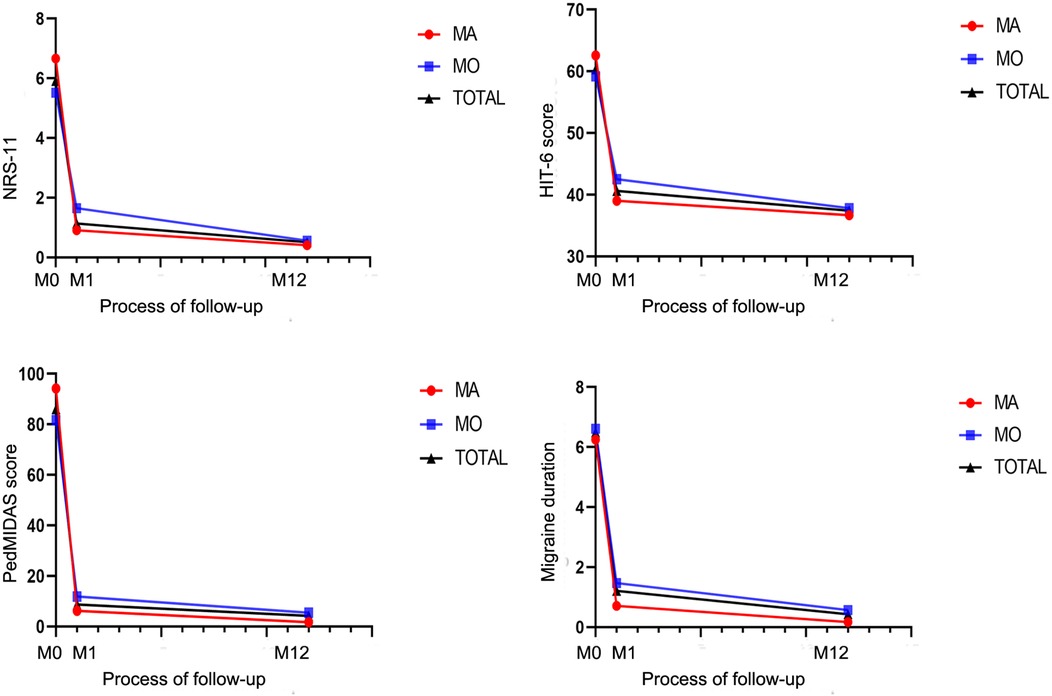

Most patients exhibited varying degrees of improvement in migraine symptoms after PFO closure. At the 1-month follow-up after the intervention, 20 patients (57.1%) achieved complete remission, and 29 (82.9%) experienced a reduction in migraine frequency of >50%. At the 12-month follow-up, 28 patients (80%) achieved complete remission, and 32 (91.4%) experienced a reduction in migraine frequency of >50%. There were no cases of worsening migraine after PFO occlusion. The NRS-11, HIT-6, PedMIDAS, migraine frequency, and migraine duration of all the children three months before the intervention, at 1 month after the intervention, and at 12 months after the intervention are shown in Table 2, which demonstrates a significant decrease in the main clinical outcome indicators of migraines from baseline to 12 months after the intervention. Notably, there were statistically significant differences between pre-intervention and one-month post-intervention data, as well as between pre-intervention and 12-month post-intervention data (p < 0.05). One year after PFO closure, only one patient continued to use the prophylactic migraine medication flunarizine, whereas two patients used analgesics solely during migraine attacks.

The reduction in NRS-11 at 12 months after intervention was more pronounced in the aura group than in the non-aura group (P < 0.05), while there were no statistically significant differences between the two groups in terms of HIT-6, PedMIDAS, and migraine duration (Figure 6, Table 4).

Figure 6. Changes in headache-related scores in children with migraine with aura and in those with migraine without aura after patent foramen ovale closure.

Table 4. Headache-related scores at different time points after patent foramen ovale closure in children with migraine with aura and in those with migraine without aura.

Our study demonstrated significant therapeutic benefits of PFO closure in pediatric migraine patients with moderate-to-large right-to-left shunts. At the 1-month follow-up after intervention, 20 patients (57.1%) achieved complete remission, and 29 (82.9%) experienced a reduction in migraine frequency of >50%. At the 12-month follow-up, 28 patients (80%) achieved complete remission, and 32 (91.4%) experienced a reduction in migraine frequency of >50%. During the 12-month follow-up period, the headache-related scores decreased significantly compared to pre-intervention levels, with statistical significance. Both the aura and non-aura groups demonstrated high response rates (83% vs. 78.3% complete remission; 100% vs. 87% achieving >50% frequency reduction), with no statistically significant intergroup differences (Figure 5, Table 3). The reduction in NRS-11 at 12 months after intervention was more pronounced in the aura group than in the non-aura group (P < 0.05), while there were no statistically significant differences between the two groups in terms of HIT-6, PedMIDAS, and migraine duration. Moreover, no serious adverse events occurred, supporting the safety of the procedure. These findings support the potential therapeutic value of PFO closure in selected pediatric migraine patients, particularly in those demonstrating medication-refractory symptoms coupled with objectively confirmed moderate-to-large right-to-left shunts.